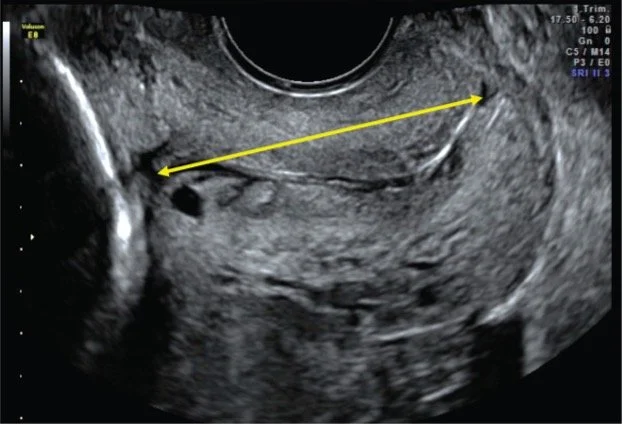

The Only One was written by composer Hannah Conway and writer Hazel Gould after 16 hours of research and interviews with patients and staff in pre-term birth clinics at Elizabeth Garett Anderson Wing, University College Hospital London. The aria is sung by a fictional patient. It explores experiences of internal vaginal ultrasound scans for the purpose of cervical measurement and assessment of pre-term birth assessment risk.

The composition will be the prelude to a training video for midwives learning internal vaginal ultrasound scanning which will be released in mid-2026.